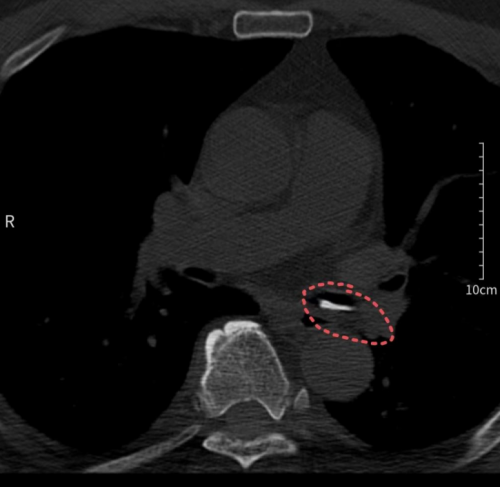

进入医院后,刘建军接受了胸部CT检查。接诊的耳鼻咽喉头颈外科副主任、副主任医师周定刚及主治医师文杰,在详细询问刘建军的经历并仔细阅读CT影像片后,发现其左侧支气管处有高密度影,但食管未见明显破损。他们迅速判断为支气管异物,并立即联系呼吸与危重症医学科进行紧急会诊。

胸部CT检查发现异物在左侧支气管为确保患者安全,医生们决定立刻为刘建军实施纤支镜下异物取出术。呼吸内镜诊疗中心副主任医师刘超群从家中赶来,迅速为刘建军进行了纤支镜检查及支气管异物取出术。术中,医生成功从患者支气管内取出两块正方形的甲鱼背壳骨片。从患者入院到异物取出,整个过程仅用时1小时,确保了患者的安全。